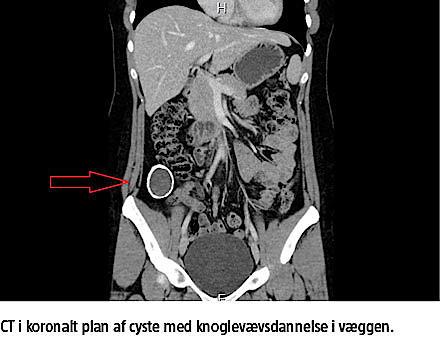

En 27-årig tidligere rask kvinde blev henvist til et kirurgisk ambulatorium med en cystisk proces i højre fossa iliaca. Patienten havde inden henvisningen været vurderet af en praktiserende gynækolog samt på et medicinsk ambulatorium. Hendes symptomer var stik og jag i maven, primært i forbindelse med bevægelse. Processen blev fundet ved CT i 2011 i forbindelse med udredning for symptomerne. På CT’en sås en cystisk process med forkalkning af væggen. Cysten var uden tegn på malignitet og fri fra naboorganer. Den blev målt til 48 × 43 × 31 mm ved en UL-undersøgelse af abdomen og blev beskrevet som en ekkotom cyste med forkalket væg i højre fossa iliaca i vinklen mellem musculus iliopsoas og musculus iliacus. Efter en konferencebeslutning blev patienten tilbudt laparoskopisk operation og fik fjernet hele processen uden komplikationer. Lokalisationen var retroperitoneal, og det videre postoperative forløb var ukompliceret.

Patologisvaret viste, at det var en benign cyste. Væggen var kalcificeret med knoglevævsdannelse

bestående af knoglemarv, knoglespange samt fibrose og var uden epitelbeklædning. Indholdet var amorft,

nekrotisk materiale uden vitale celler og uden

malignitet.